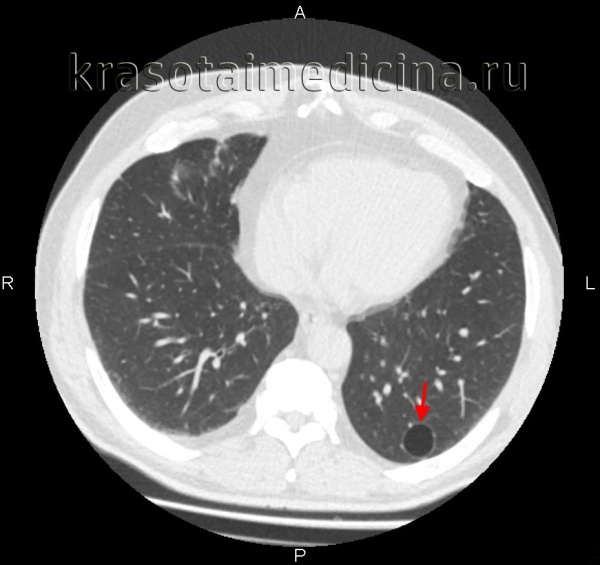

- Компьютерная томография. КТ ОГК производится для уточнения характера повреждений, выявления ателектазов, пневмо- и гемоторакса, других патологий, выполняется нативно или с контрастом. Пациентам также могут быть показаны КТ легких или КТ средостения. Для детализации изменений, обнаруженных на рентгенограммах костей лица, могут быть назначены КТ орбиты и другие исследования.

Кроме этого, буллы могут быть солитарными и множественными, одно– и двусторонними, напряженными и ненапряженными. По распространенности в легком дифференцируют локализованную (в пределах 1-2-х сегментов) и генерализованную (с поражением более 2-х сегментов) буллезную эмфизему. В зависимости от размера буллы могут быть мелкими (диаметром до 1 см), средними (1-5 см), крупными (5-10 см) и гигантскими (10-15 см в диаметре). Буллы могут располагаться как в неизмененном легком, так и в легких, пораженных диффузной эмфиземой.

Диагностика буллезной эмфиземы легких основывается на клинических, функциональных и рентгенологических данных. Курация больного осуществляется пульмонологом, а при развитии осложнений – торакальным хирургом. Рентгенография легких не всегда эффективна в выявлении буллезной эмфиземы легких. В то же время, возможности лучевой диагностики существенно расширяет внедрение в практику КТ высокого разрешения. На томограммах буллы определяются как тонкостенные полости с четкими и ровными контурами. При сомнительном диагнозе удостовериться в наличии булл позволяет диагностическая торакоскопия.